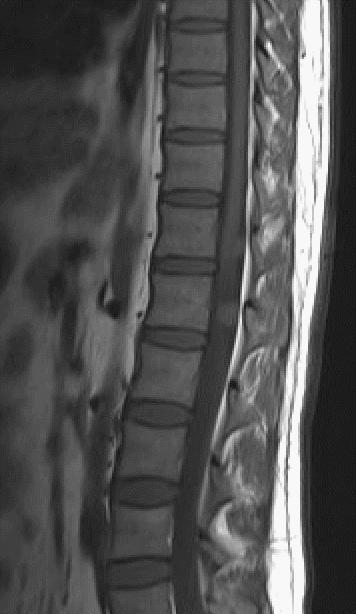

MRI

T1WI矢状位,定位图中所示最下一节为腰5椎体。T2WI、T2WI压脂、T2WI轴位、T1WI增强